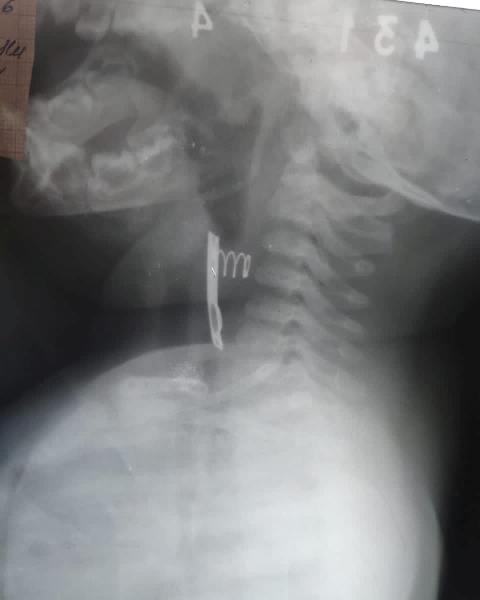

Хирурги ачинского филиала краевого перинатального центра спасли жизнь 11-месячного пациента. Как рассказали в Минздраве региона, ребёнок проглотил металлическую пластину с пружиной от зарядного устройства для батареек. Ситуацию осложняло то, что малыш был контактным по Covid-19, поэтому операцию проводили со всеми необходимыми противовирусными предосторожностями.

Благодаря слаженным действиям бригады детских хирургов, анестезиологов-реаниматологов и медсестер инородный предмет был удален из дыхательных путей мальчика эндоскопически. Сложное оперативное вмешательство не потребовалось. Врачи заверили, что восстановление малыша должно быть быстрым и легким.